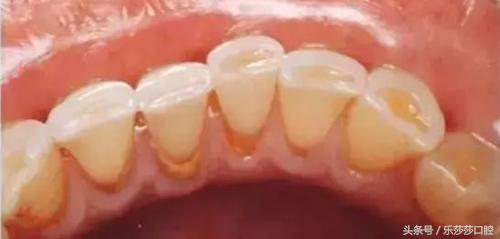

三、牙齿表面的牙菌斑(黄色):这种黄色东西是人类口腔中繁殖的大量「细菌」,跟「口腔卫生」有直接关系。它会在牙龈部位「扎营繁殖」,产生一种「酸性」物质,这种酸性物质会「腐蚀」牙齿导致蛀洞,另外,还会导致牙周炎。